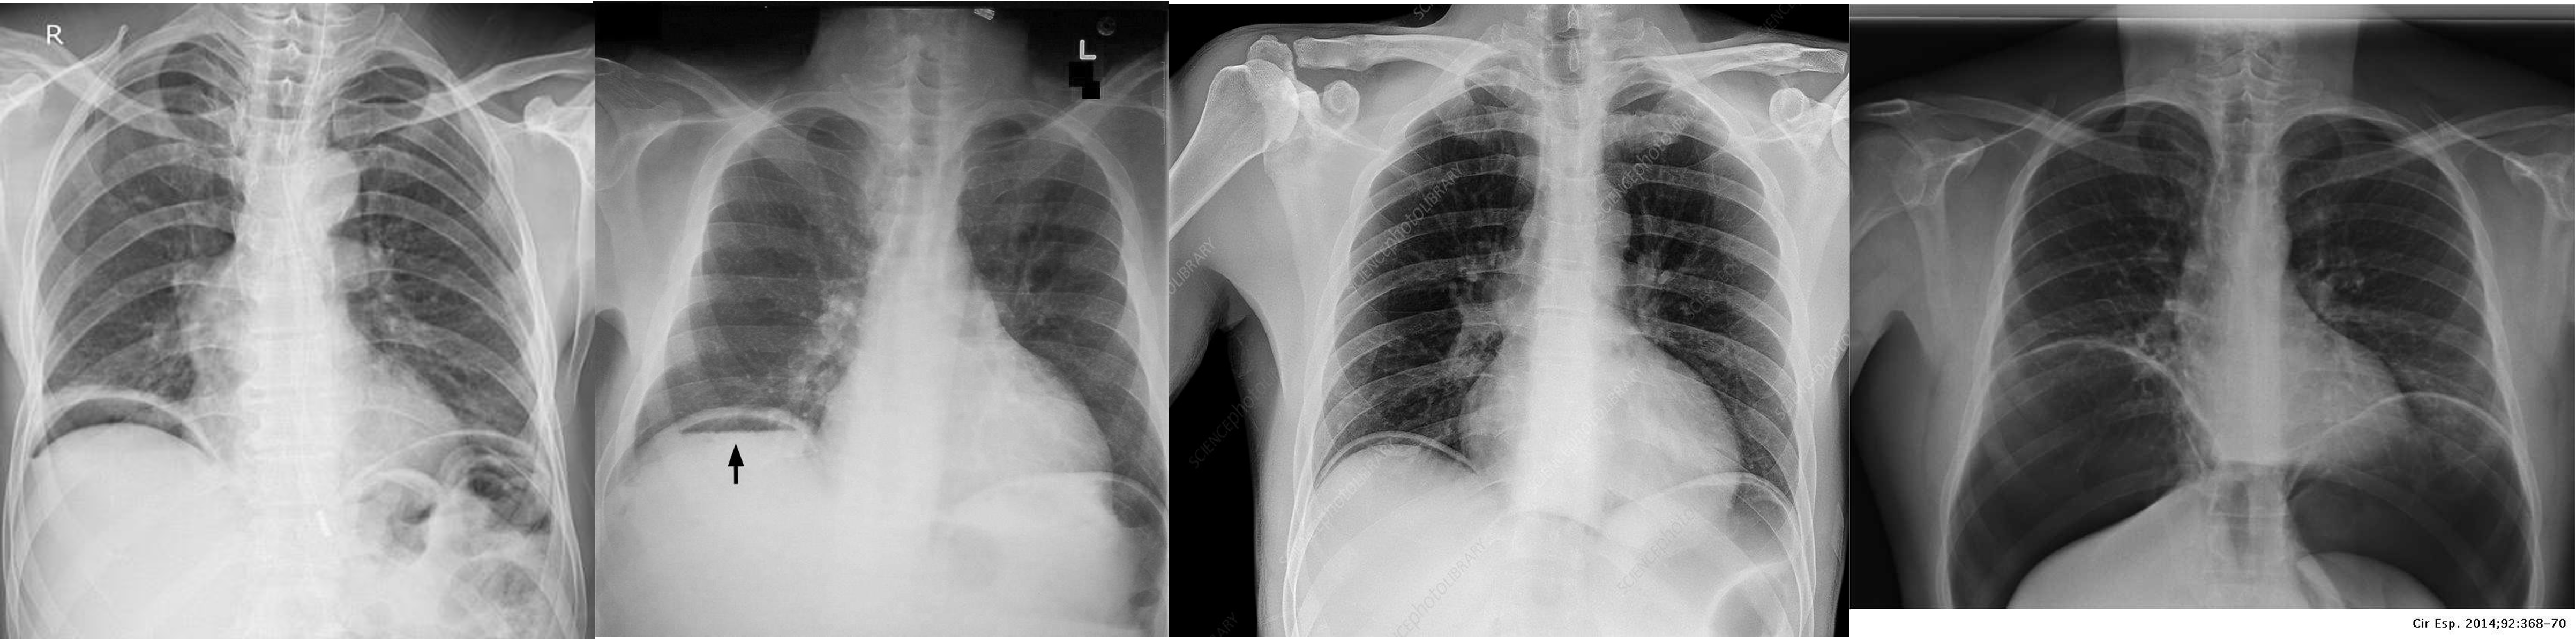

Chest Imaging

- Pneumothorax - Right lung

- Pneumothorax - Left lung - mediastinum pushed

- Pneumothorax - RT